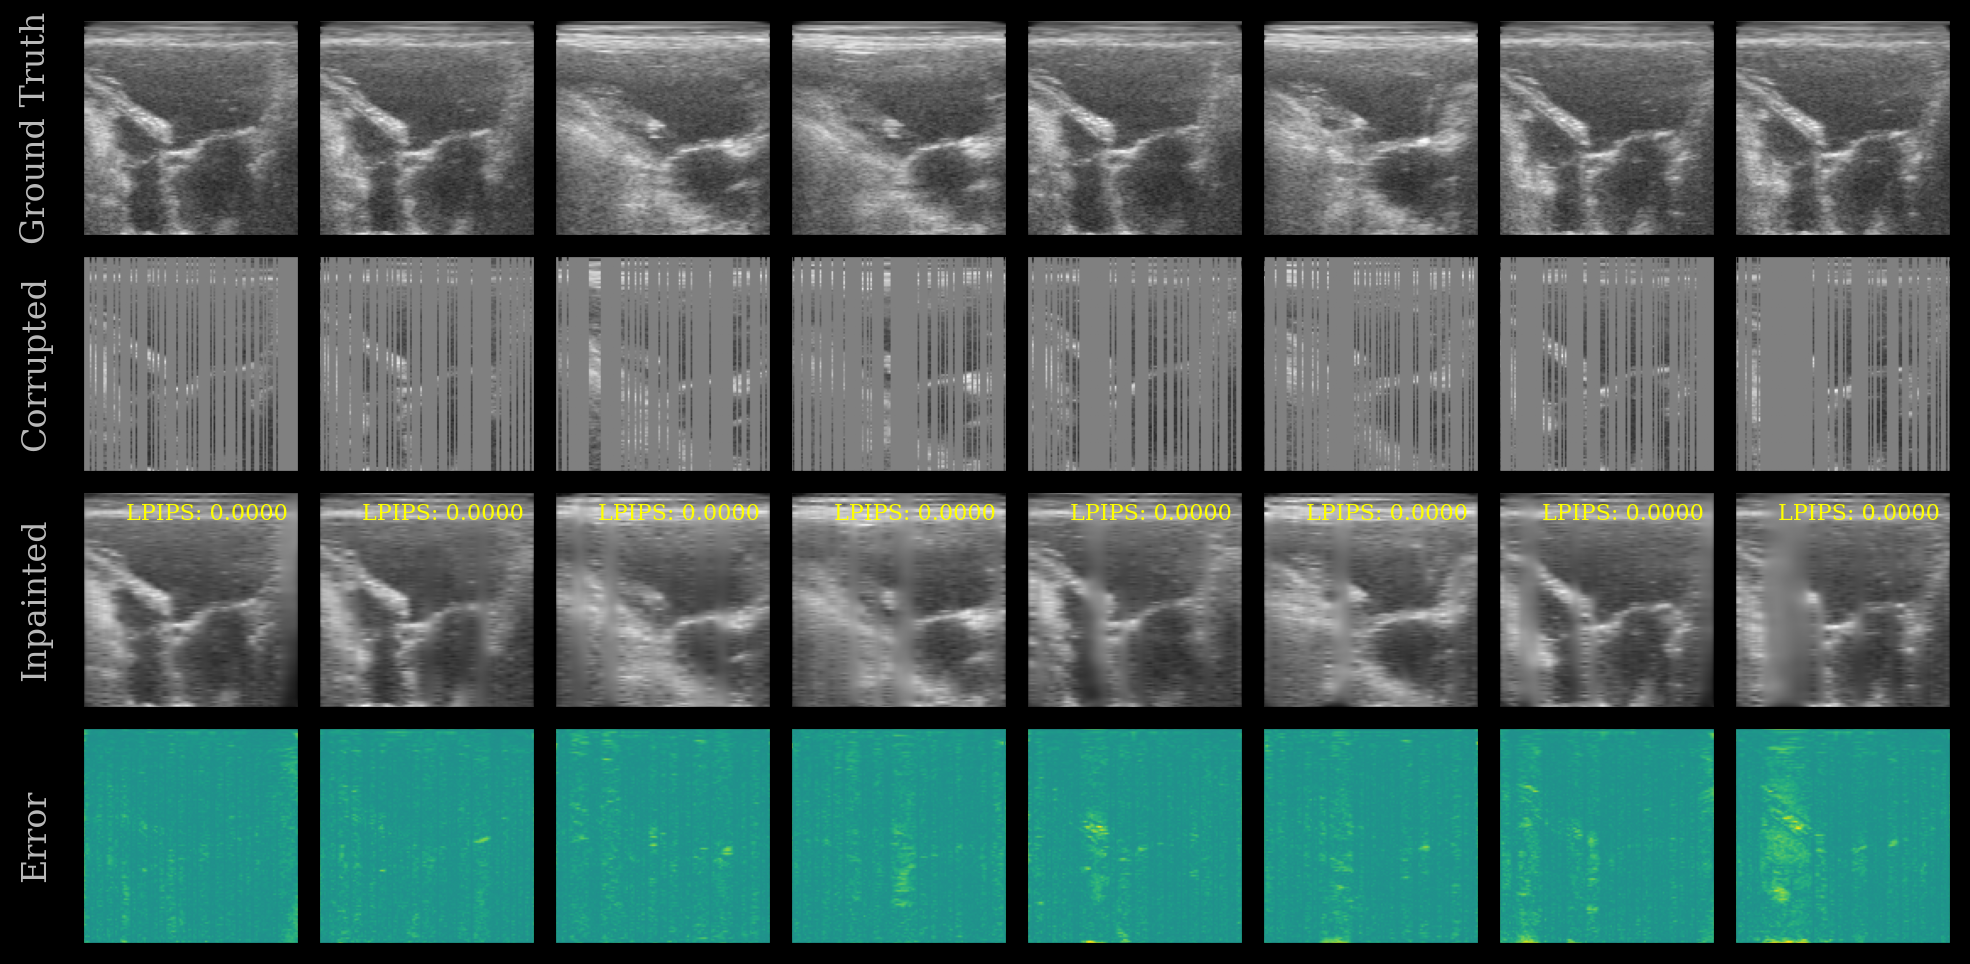

We plot the ground truth, corrupted, inpainted, and error images. The LPIPS score is shown on each inpainted image. Note that this model was trained on the EchoNet-Dynamic dataset, whereas we are testing now on the CAMUS dataset.

[10]:

error = ops.abs(batch - inpainted)

imgs = ops.concatenate([batch, corrupted, inpainted, error], axis=0)

imgs = ops.convert_to_numpy(imgs)

cmaps = ["gray"] * (3 * n_imgs) + ["viridis"] * n_imgs

fig, _ = plot_image_grid(

imgs,

vmin=-1,

vmax=1,

ncols=n_imgs,

remove_axis=False,

cmap=cmaps,

figsize=(n_imgs * 2, 6),

)

titles = ["Ground Truth", "Corrupted", "Inpainted", "Error"]

for i, ax in enumerate(fig.axes[: len(titles) * n_imgs]):

if i % n_imgs == 0:

ax.set_ylabel(titles[i // n_imgs])

# Show LPIPS score on each inpainted image

for ax, lpips_score in zip(fig.axes[n_imgs * 2 : 3 * n_imgs], lpips_scores):

ax.text(

0.95,

f"LPIPS: {float(lpips_score):.4f}",

ha="right",

va="top",

transform=ax.transAxes,

fontsize=8,

color="yellow",

fig.savefig("./inpainting_results.png", dpi=200, bbox_inches="tight")

plt.close(fig)

UNet Inpainting Results